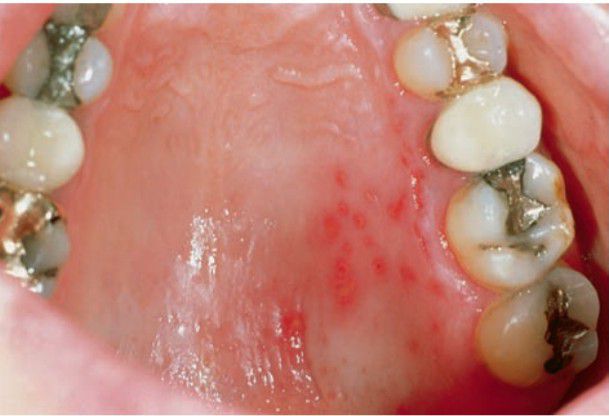

Herpes zoster infection of palate

Zoster is essentially a condition of the older adult population and of individuals who have compromised immune response